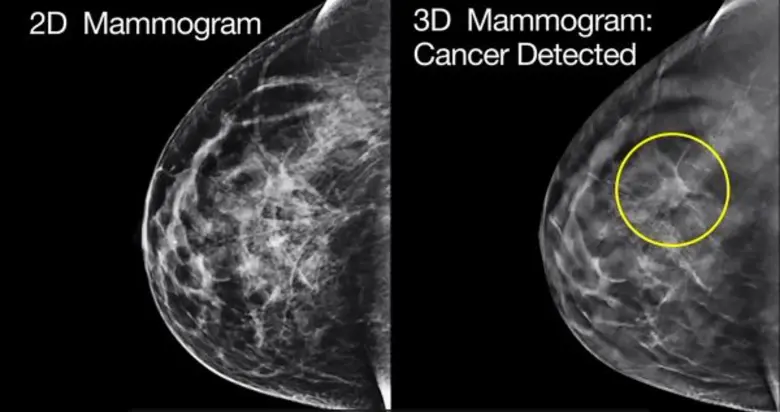

อย่างไรก็ดี ทั้งสองวิธียังมีข้อจำกัดในการตรวจคัดกรองให้กับประชาชน กล่าวคือการตรวจด้วยบุคลากรทางแพทย์โดยใช้การคลำมักมีปัญหาเรื่องความแม่นยำ เนื่องจากเป็นการตรวจที่ต้องใช้ความรู้สึกและความชำนาญเฉพาะตัวของบุคลากรแต่ละคน ผลที่ออกมามักมีความแตกต่างกันค่อนข้างมาก นอกจากนี้ยังมีข้อจำกัดเรื่องจำนวนบุคลากรที่ไม่เพียงพอ ขณะที่การตรวจคัดกรองมะเร็งด้วยแมมโมแกรมนั้น แม้จะเป็นวิธีที่มีประสิทธิภาพดีที่สุดในปัจจุบัน แต่มีต้นทุนสูงไม่คุ้มค่าสำหรับประเทศไทย หากจะนำมาเป็นนโยบายใช้ตรวจคัดกรองให้กับผู้หญิงทุกคนที่มีอายุตั้งแต่ 40-50 ปีขึ้นไป

คำแนะนำเหล่านี้เป็นผลการศึกษาจากประเทศฝั่งตะวันตก ซึ่งผู้หญิงกลุ่มนี้มีลักษณะ เนื้อเต้านมไม่หนาแน่น มีส่วนประกอบของไขมันเป็นส่วนใหญ่ เมื่อมีความผิดปกติของมะเร็งจะเห็นได้ชัดเจนด้วยการตรวจแมมโมแกรมเพียงอย่างเดียว ส่วนผู้หญิงไทยหรือเอเชียมีลักษณะเนื้อเต้านมที่หนาแน่นกว่า มีไขมันน้อยกว่า ทำให้เห็นความผิดปกติของมะเร็งได้ยากขึ้น ดังนั้น ในประเทศไทยมักต้องใช้เครื่องอัลตร้าซาวด์ตรวจร่วมด้วย ซึ่งประเทศทางตะวันตกจะใช้การตรวจทั้งสองวิธีร่วมกันก็ต่อเมื่อต้องการวินิจฉัยความผิดปกติภายหลังการตรวจคัดกรองเบื้องต้นเท่านั้น ทำให้การตรวจคัดกรองมะเร็งเต้านมของไทยมีค่าใช้จ่ายที่สูงขึ้น และจำเป็นต้องใช้รังสีแพทย์ที่มีจำกัดในการทำ